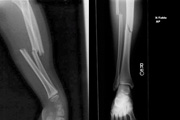

卢克肖伤腿X光照片曝光 曼联为其请心理医生

近日,卢克肖伤腿X光照片曝光,两处骨折清晰可见。根据《每日邮报》消息,惨遭断腿的曼联后卫卢克肖将会在荷兰面临第二轮手术。同时曼联将给这名后防大将寻找一名心理医生帮助其恢复。...

惨!曼联天才卢克肖遭断腿恐赛季报销

北京时间9月16日,2015-16赛季欧洲冠军联赛B组展开首轮争夺。PSV埃因霍温队坐镇主场飞利浦大球场迎战曼联队。比赛第14分钟,卢克-肖遭遇严重受伤,右腿严重弯曲。从回放的镜头来看卢克-肖极有可能遭遇右小腿骨折,按照正常状况2015年基本报废,甚至赛季报销。...